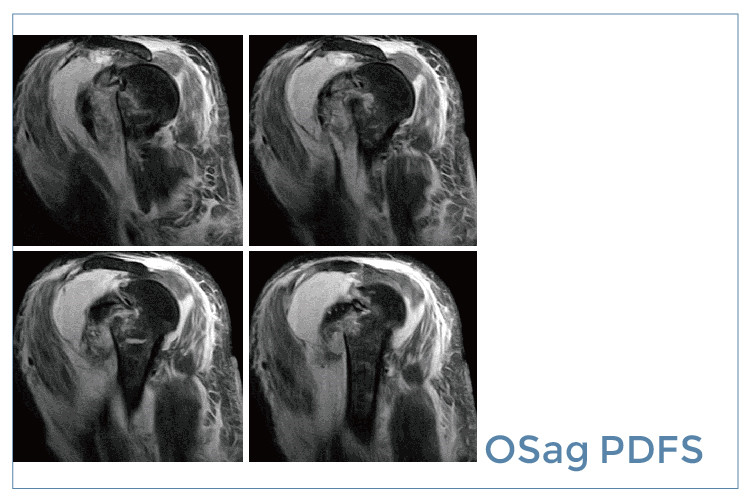

【朗润影像档案】20190830磁共振影像病例结果讨论